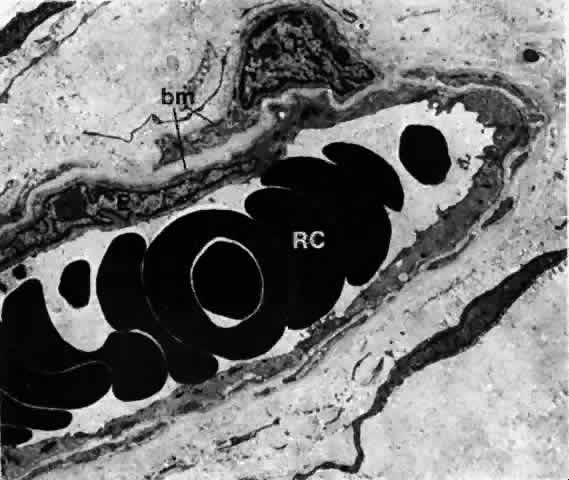

Small blood vessels of the bulbar conjunctiva have arteriovenous communications.14 The communicating vessels may be tortuous and uneven in caliber, but they usually are larger in diameter than capillaries. Each gives off capillary branches proximally and receives capillaries distally. They are not true arteriovenous anastomoses because they do not possess muscular walls that would render them capable of responding to chemical agents. Occasionally, the conjunctival blood vessels may become damaged, causing a spontaneous subconjunctival hemorrhage. These hemorrhages have very few associations with systemic diseases and usually absorb in a matter of a week or two. Electron microscopy has revealed that a majority of the capillaries often have a thick, continuous wall but few fenestrations (Fig. 20). Larger vessels with smooth muscles are also present.

Fig. 20. A blood capillary in the stroma of bulbar conjunctiva. This is a nonfenestrated type, but there also is a fenestrated type in the conjunctival stroma. Both endothelium (E) and pericytes (P) are surrounded by a basement membrane (bm), and the lumen contains erythrocytes (RC). (× 6300)